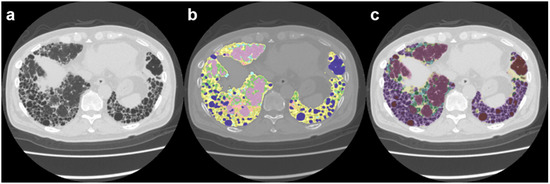

Artificial Intelligence Unveils the Unseen: Mapping Novel Lung Patterns in Bronchiectasis via Texture Analysis

Background and Objectives: Thin-section CT (TSCT) is currently the most sensitive imaging modality for detecting bronchiectasis. However, conventional TSCT or HRCT may overlook subtle lung involvement such as alveolar and interstitial changes. Artificial Intelligence (AI)-based analysis offers the potential to identify novel information [...] Read more.

Background and Objectives: Thin-section CT (TSCT) is currently the most sensitive imaging modality for detecting bronchiectasis. However, conventional TSCT or HRCT may overlook subtle lung involvement such as alveolar and interstitial changes. Artificial Intelligence (AI)-based analysis offers the potential to identify novel information on lung parenchymal involvement that is not easily detectable with traditional imaging techniques. This study aimed to assess lung involvement in patients with bronchiectasis using the Bronchiectasis Radiologically Indexed CT Score (BRICS) and AI-based quantitative lung texture analysis software (IMBIO, Version 2.2.0). Methods: A cross-sectional study was conducted on 45 subjects diagnosed with bronchiectasis. The BRICS severity score was used to classify the severity of bronchiectasis into four categories: Mild, Moderate, Severe, and tractional bronchiectasis. Lung texture mapping using the IMBIO AI software tool was performed to identify abnormal lung textures, specifically focusing on detecting alveolar and interstitial involvement. Results: Based on the Bronchiectasis Radiologically Indexed CT Score (BRICS), the severity of bronchiectasis was classified as Mild in 4 (8.9%) participants, Moderate in 14 (31.1%), Severe in 11 (24.4%), and tractional in 16 (35.6%). AI-based lung texture analysis using IMBIO identified significant alveolar and interstitial abnormalities, offering insights beyond conventional HRCT findings. This study revealed trends in lung hyperlucency, ground-glass opacity, reticular changes, and honeycombing across severity levels, with advanced disease stages showing more pronounced structural and vascular alterations. Elevated pulmonary vascular volume (PVV) was noted in cases with higher BRICSs, suggesting increased vascular remodeling in severe and tractional types. Conclusions: AI-based lung texture analysis provides valuable insights into lung parenchymal involvement in bronchiectasis that may not be detectable through conventional HRCT. Identifying significant alveolar and interstitial abnormalities underscores the potential impact of AI on improving the understanding of disease pathology and disease progression, and guiding future therapeutic strategies. Full article

Show Figures

Figure 1